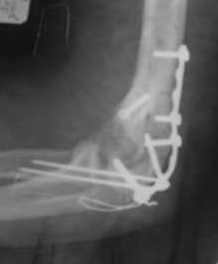

Уважаемые коллеги! Нужен Ваш совет, Подскажите пожалуйста, как можно в дальнейшем этому больному помочь. В марте первая операция, пришлось оперировать на 16 сутки в виду инфицированных садин и анемии. Заживление первичным натяжением,раняя разработка после операции, а через 2 нед болевой синдром,и постепенно движения в локтевом суставе ограничились до полного анкилоза. Повторно через 4 месяца вторая операция" артролиз,удаление оссификатов, удаление фиксаторов, реостеосинтез этой же реконструкционной пластиной и винтом" интраоперационно после удаления оссификатов и фиксаторов обнаружил, что перелом не сросшиеся, поэтому пришлось синтезировать заново. Зажило рана первично, объем движений в локтевом суставе сгибание 70, разгибание160, ротационные движения востановились полностью,вроде бы успокоились. Опять постепенно в течении 8 нед после повторной операции постепенно движения ограничились до 80 - 110, на снимке оссификат. Снимки во вложении, буду рад Вашим советам. Спасибо!С уважением Шухрат.